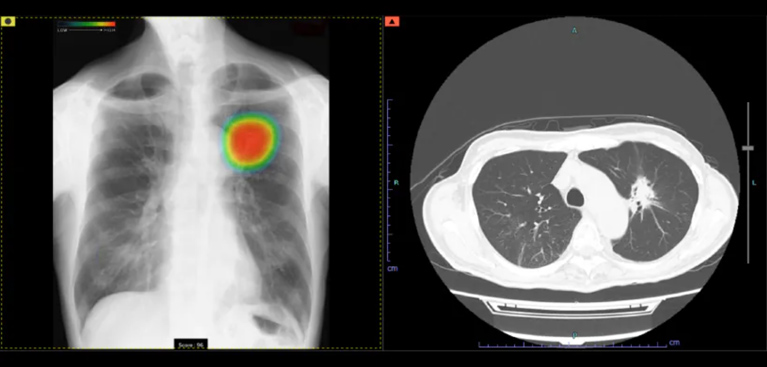

AI診断システムCXR-AID(富士フィルム社)を導入しております。胸部レントゲン画像をAIによって解析し、結節や腫瘤陰影・浸潤影(炎症)・気胸などが疑われる場合、色付けによって表示されます。これにより医師とAIのダブルチェックが可能となり見落としのリスク軽減・初期段階でキャッチできるなどのメリットがあります。

CXR-AIDは、AIが胸部の画像を数十秒で読み取り、気になる可能性のある部分をマークして表示します。医師はAIが示した箇所を確認しながら診断を行うため、見落としが少なく、より正確な診断につながります。AIと医師が一緒にチェックすることで、病気を早めに見つけられる体制を整えています。

検出対象となるのは、主要な肺疾患に関連する画像所見である「結節・腫瘤影」、「浸潤影」、および「気胸」の3つです。

0~100に分けられた確信度スコアの最大値が数値として表示されます。

胸部レントゲン所見のスコア値は、数値が高いほど「治療が必要かもしれない病変」の可能性が高くなります。そのため、スコア値が高い場合には胸部CTによる詳しい検査を受けていただくことがあります。